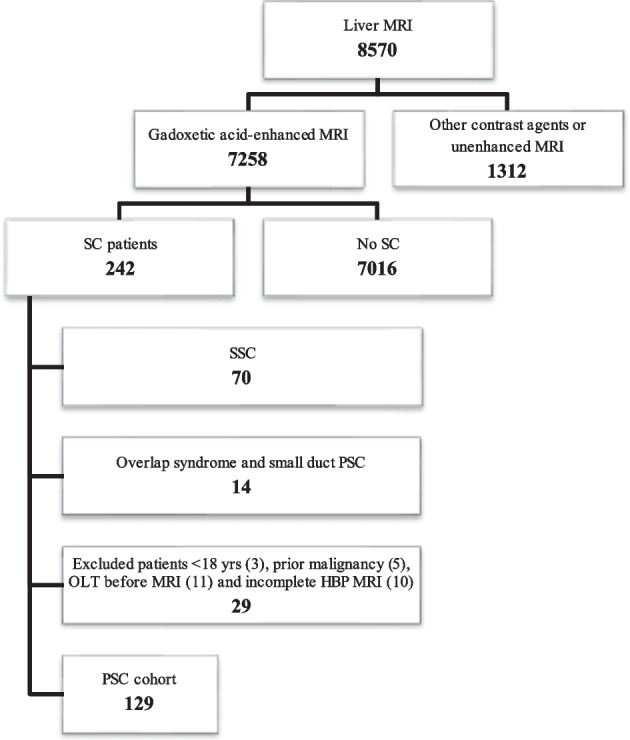

Our institutional review board approved this retrospective, single-center study. All patients gave written, informed consent for MRI and interventional procedures. Only patients with confirmed PSC according to EASL guidelines [ref. 5, ref. 6] who underwent GA-MRI between Oct 2007 and March 2022 were included. We excluded patients with secondary sclerosing cholangitis, small-duct PSC, or confounding liver illnesses and who were under the age of 18 and/or had incomplete GA-MRI exams. Autoimmune hepatitis/PSC overlap syndrome, and other concomitant liver diseases, such as primary biliary cholangitis (PBC), hepatitis B or C infection, Wilson’s disease, haemochromatosis, autoimmune hepatitis, alcoholic liver disease, NAFLD/NASH, previous orthotopic liver transplantation OLT, previous choledochojejunostomy, cholangiocellular carcinoma, hepatocellular carcinoma, and cirrhotic decompensation, at the time of inclusion were considered confounding liver illnesses [ref. 6]. Importantly, the diagnosis of PSC was made only after potential causes of secondary sclerosing cholangitis (SSC) had been ruled out. These included IgG4-related cholangitis (IRC), sclerosing cholangitis of the critically ill patient (SC-CIP), or surgical/mechanical, toxic/drug-induced, infectious, and other immune-mediated and ischemic etiologies [ref. 21] (Fig. 1).